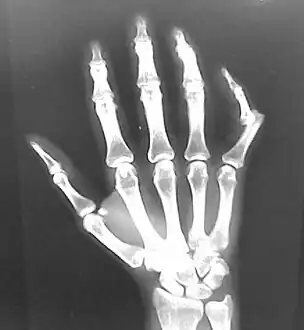

| Joint dislocation | |

![]() | |

| A traumatic dislocation of the tibiotarsal joint of the ankle with distal fibular fracture. Open arrow marks the tibia and the closed arrow marks the talus. | |